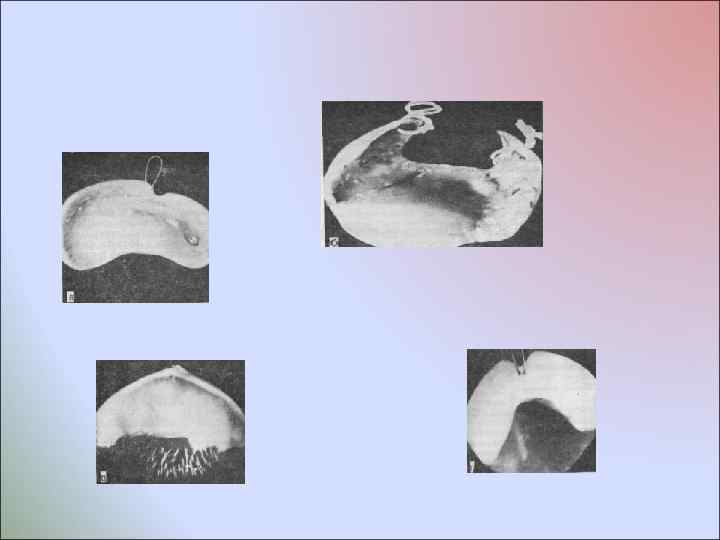

В родильном доме в первые часы после рождения ребенок обеспечивается ортопедическим аппаратом —преформированной пластинкой, которая не только разобщает носовую и ротовую полости, но и стимулирует рост недоразвитых и слаборазвитых фрагментов верхней челюсти, изменяя их положение. После осмотра и обследования новорожденного в присутствии неонатолога, соблюдая правила асептики с помощьюэластичной массы и специальной ложки получают оттиск с верхней челюсти. Методика получения слепка такова: тщательно приготовляют оттискную массу, которую накладывают на хорошо подобранную ложку с отводным каналом. С целью предупреждения асфиксии необходимо вызвать громкий плач ребенка путем пальцевого давления на пяточную кость. Во время плача ложку с оттискной массой вводят в полость рта ребенка и накладывают на область альвеолярных отростков справа и слева. При этом вначале надавливают пальцем на дистальный отдел ложки, в результате чего оттискная масса перемещается кпереди, под фрагменты верхней губы и через отводной канал в полость рта.

В родильном доме в первые часы после рождения ребенок обеспечивается ортопедическим аппаратом —преформированной пластинкой, которая не только разобщает носовую и ротовую полости, но и стимулирует рост недоразвитых и слаборазвитых фрагментов верхней челюсти, изменяя их положение. После осмотра и обследования новорожденного в присутствии неонатолога, соблюдая правила асептики с помощьюэластичной массы и специальной ложки получают оттиск с верхней челюсти. Методика получения слепка такова: тщательно приготовляют оттискную массу, которую накладывают на хорошо подобранную ложку с отводным каналом. С целью предупреждения асфиксии необходимо вызвать громкий плач ребенка путем пальцевого давления на пяточную кость. Во время плача ложку с оттискной массой вводят в полость рта ребенка и накладывают на область альвеолярных отростков справа и слева. При этом вначале надавливают пальцем на дистальный отдел ложки, в результате чего оттискная масса перемещается кпереди, под фрагменты верхней губы и через отводной канал в полость рта.

Плач ребенка должен продолжаться до затвердевания оттискной массы, когда она теряет свою текучесть, вследствие чего устраняется угроза попадания гранул оттискной массы в дыхательные пути и пищеварительный тракт. Вывести оттиск из полости рта ребенка несложно. Оттиск, как правило, выводится одним конгломератом. На нем должны быть точно отображены контуры альвеолярных и небных отростков правой и левой половин верхней челюсти, хорошо контурироваться их вестибулярные границы, размеры, характер и протяженность расщелины, а также средний отдел твердого и мягкого неба. Рельеф оттиска зависит от характера расщелины. Затем отливают гипсовую модель и проводят ее преформацию в трех взаимно перпендикулярных плоскостях.

Плач ребенка должен продолжаться до затвердевания оттискной массы, когда она теряет свою текучесть, вследствие чего устраняется угроза попадания гранул оттискной массы в дыхательные пути и пищеварительный тракт. Вывести оттиск из полости рта ребенка несложно. Оттиск, как правило, выводится одним конгломератом. На нем должны быть точно отображены контуры альвеолярных и небных отростков правой и левой половин верхней челюсти, хорошо контурироваться их вестибулярные границы, размеры, характер и протяженность расщелины, а также средний отдел твердого и мягкого неба. Рельеф оттиска зависит от характера расщелины. Затем отливают гипсовую модель и проводят ее преформацию в трех взаимно перпендикулярных плоскостях.

Сегменты преформированной модели соединяются между собой посредством пластинки, которую изготовляют из любого базисного материала. В переднем отделе ортопедического аппарата по проекции расщелины вваривают металлическую фиксирующую петлю из ортодонтической проволоки диаметром 0, 6 мм. Полимеризацию преформированного ортопедического аппарата проводят в специальной кювете под давлением. Затем осуществляют шлифовку и полировку аппарата. Готовый аппарат вводят в полость рта ребенка, контролируют его границы и степень прилегания к альвеолярным отросткам верхней челюсти, после чего аппарат фиксируют к эластичной давящей повязке посредством полосок лейкопластыря, проведенных через металлическую петлю. Введенный в полость рта ортопедический аппарат вызывает у младенца раздражение слизистой оболочки, и у него появляются первые сосательные движения. Медицинский персонал родильного отделения приготавливает 10 г сцеженного молока и проводит первое кормление ребенка с помощью соски и аппарата. Активность сосания повышается с каждой минутой, и к концу кормления ребенок сосет ровно и спокойно. Медицинский персонал родильного отделения и мать получают инструкции о режиме пользования преформированным ортопедическим аппаратом и правилах туалета полости рта.

Сегменты преформированной модели соединяются между собой посредством пластинки, которую изготовляют из любого базисного материала. В переднем отделе ортопедического аппарата по проекции расщелины вваривают металлическую фиксирующую петлю из ортодонтической проволоки диаметром 0, 6 мм. Полимеризацию преформированного ортопедического аппарата проводят в специальной кювете под давлением. Затем осуществляют шлифовку и полировку аппарата. Готовый аппарат вводят в полость рта ребенка, контролируют его границы и степень прилегания к альвеолярным отросткам верхней челюсти, после чего аппарат фиксируют к эластичной давящей повязке посредством полосок лейкопластыря, проведенных через металлическую петлю. Введенный в полость рта ортопедический аппарат вызывает у младенца раздражение слизистой оболочки, и у него появляются первые сосательные движения. Медицинский персонал родильного отделения приготавливает 10 г сцеженного молока и проводит первое кормление ребенка с помощью соски и аппарата. Активность сосания повышается с каждой минутой, и к концу кормления ребенок сосет ровно и спокойно. Медицинский персонал родильного отделения и мать получают инструкции о режиме пользования преформированным ортопедическим аппаратом и правилах туалета полости рта.

С учетом топографии расщелины выделяют шесть классов преформированных ортопедических аппаратов: I класс — аппараты для детей с правосторонней сквозной расщелиной губы, альвеолярного отростка, твердого и мягкого неба; II класс — аппараты для детей с левосторонней сквозной расщелиной верхней губы, альвеолярного отростка, твердого и мягкого неба; III класс — аппараты для детей с двусторонней сквозной расщелиной верхней губы, альвеолярного отростка, твердого и мягкого неба; IV класс — аппараты для детей со срединной несквозной расщелиной твердого и мягкого неба; V класс — аппараты для детей с расщелиной губы, альвеолярного отростка и переднего отдела твердого неба; VI класс — аппараты для детей с несквозной одно- и двусторонней расщелиной губы, альвеолярного отростка, переднего отдела неба, сочетающейся со срединной расщелиной заднего отдела твердого и полной расщелиной мягкого неба.

С учетом топографии расщелины выделяют шесть классов преформированных ортопедических аппаратов: I класс — аппараты для детей с правосторонней сквозной расщелиной губы, альвеолярного отростка, твердого и мягкого неба; II класс — аппараты для детей с левосторонней сквозной расщелиной верхней губы, альвеолярного отростка, твердого и мягкого неба; III класс — аппараты для детей с двусторонней сквозной расщелиной верхней губы, альвеолярного отростка, твердого и мягкого неба; IV класс — аппараты для детей со срединной несквозной расщелиной твердого и мягкого неба; V класс — аппараты для детей с расщелиной губы, альвеолярного отростка и переднего отдела твердого неба; VI класс — аппараты для детей с несквозной одно- и двусторонней расщелиной губы, альвеолярного отростка, переднего отдела неба, сочетающейся со срединной расщелиной заднего отдела твердого и полной расщелиной мягкого неба.